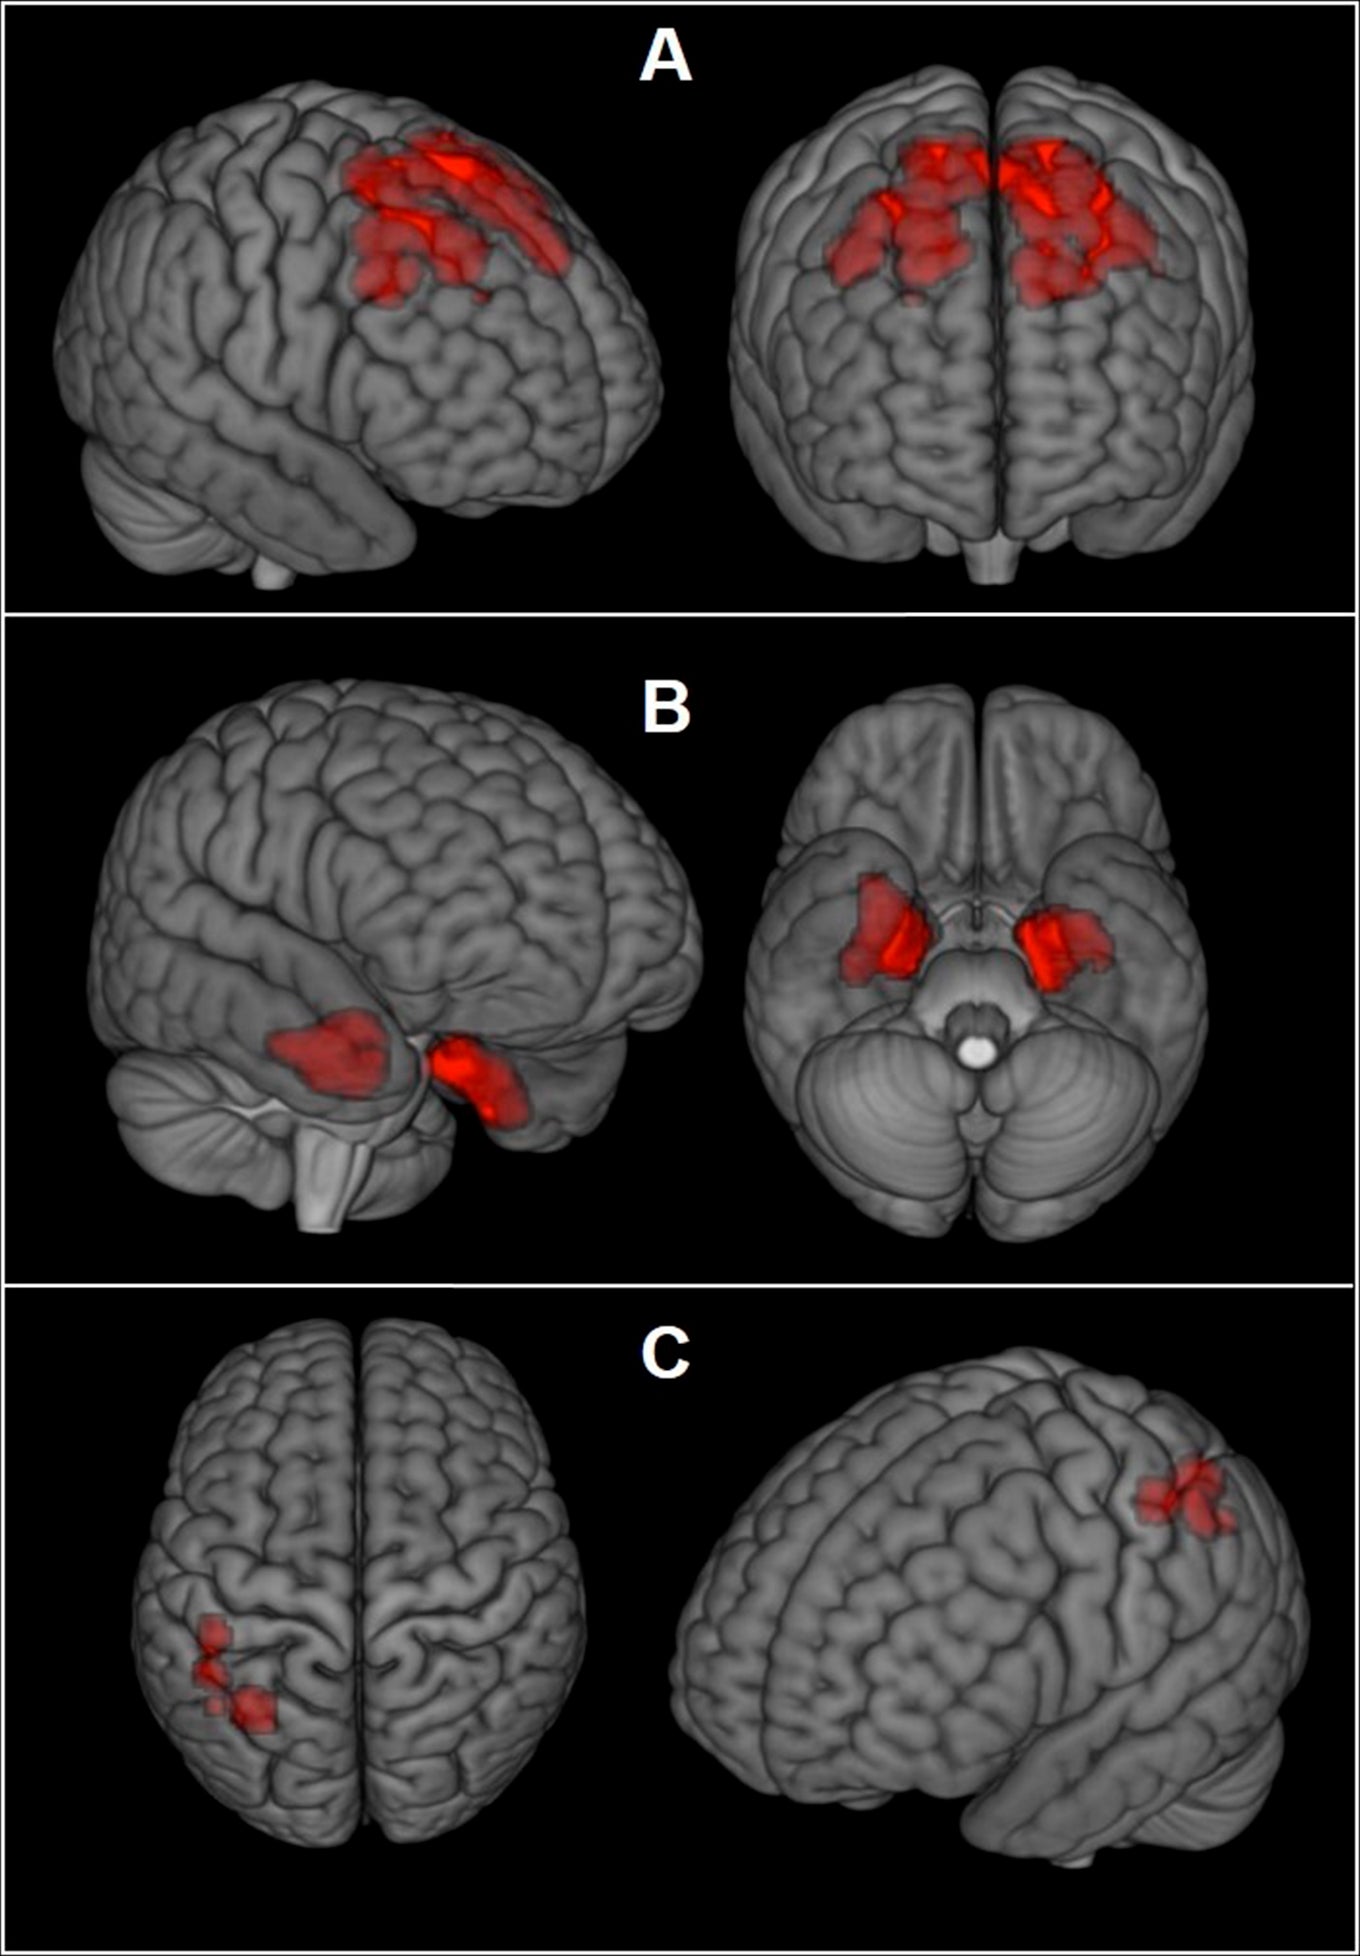

brain scan ptsd imaging medical research now doctors injuries differentiate traumatic between shows help neuro tbi

brain scan inflammation study social hierarchy wellcome health examines known place after fmri may identify researchers spreads injury anatomy determining